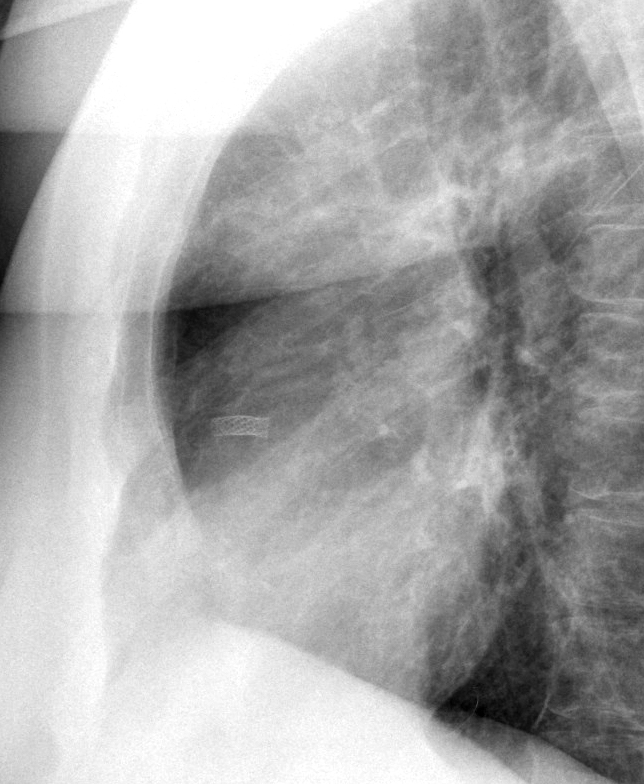

Gallery Cardiac Other coronary stent

coronary stent